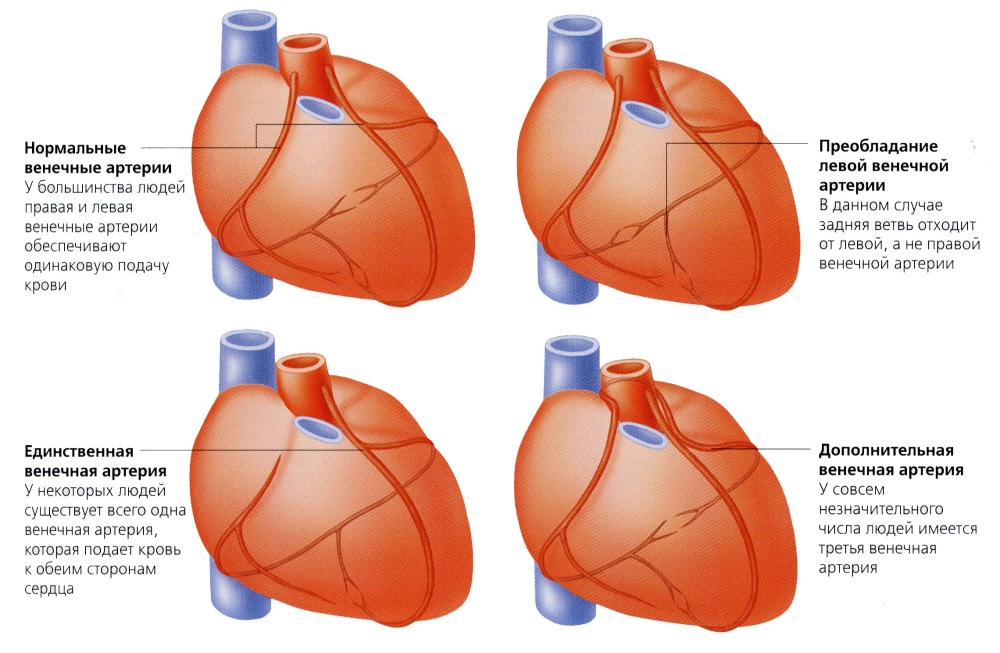

Анатомия коронарных артерий: КТ-изображения

Раздел: Снимки успеха